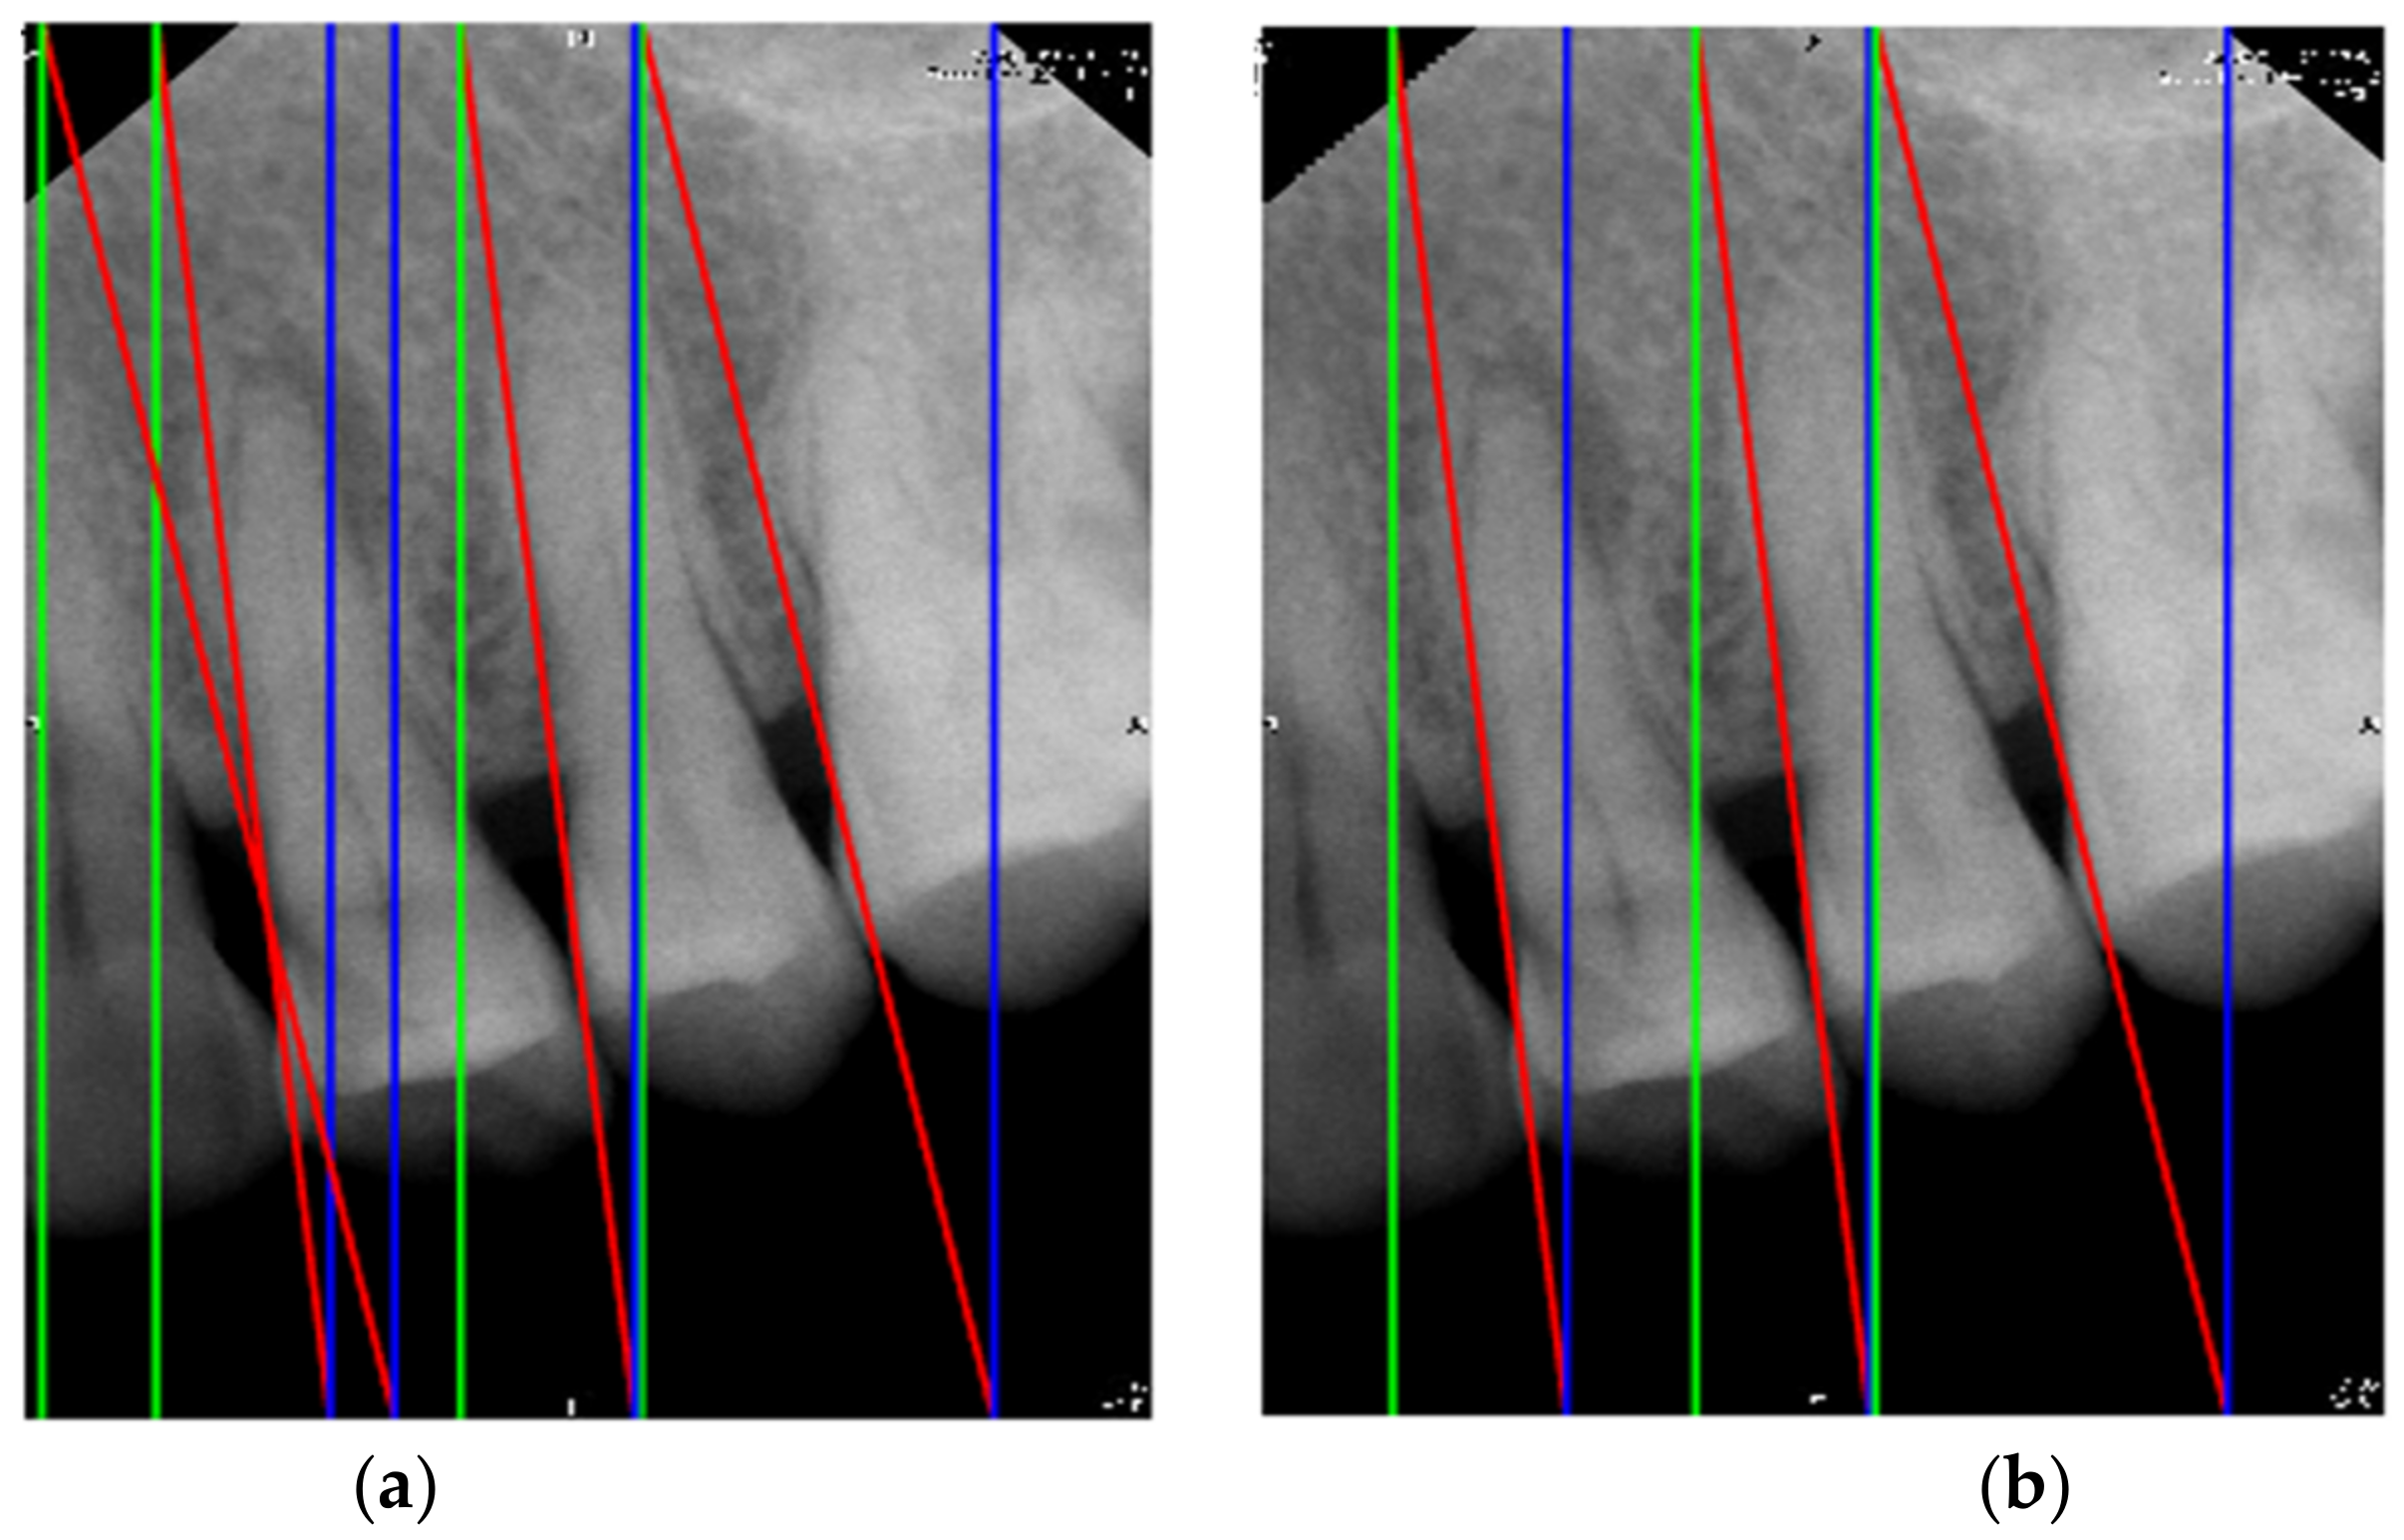

- In the image cropping preprocessing part, this study adds the adaptive threshold and angle rotation technology. Compared with the existing methods, this method significantly improves the image clarity and accuracy of a single tooth image.

2.1. Image Segmentation and Retouching

2.1.1. Vertical Cutting

2.1.2. Image Masks